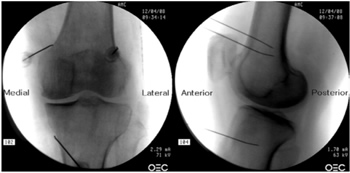

16. Kim DH, Lee MS, Lee S, Yoon SH, Shin JW, Choi SS. A prospective randomized comparison of the efficacy of ultrasound- vs fluoroscopy- guided genicular nerve block for chronic knee osteoarthritis. Pain Physician. 2019;22(2):139-46.